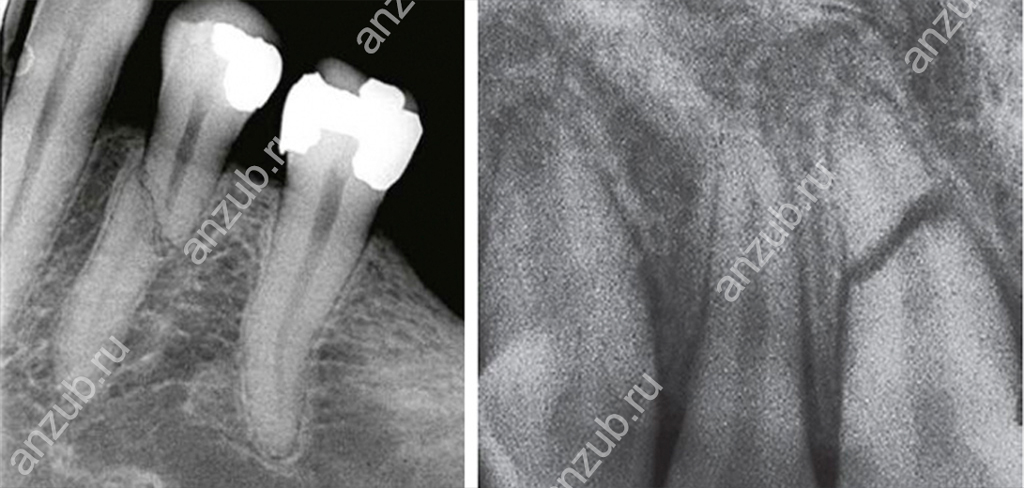

Наиболее информативным методом диагностики будет рентген или, лучше всего, компьютерная томография. С их помощью можно оценить не только место перелома и линию разлома, но и состояние окружающих тканей.

Различают несколько видов перелома:

- продольный, когда корень разломился на две части и разлом проходит по коронке тоже,

- поперечный, или горизонтальный разлом, когда отделяется верхушка или две трети,

- диагональный, или косой,

- множественные повреждения с образованием осколков.

Также есть деление переломов по расположению вдоль корня: отлом верхушки, трещина во второй трети или травма верхней трети.